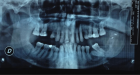

Sagittal split osteotomy (SSO) of the mandible is still an important part of orthognathic surgery, but “bad split” fractures that happen during the surgery are still a big problem. This report describes a rare case of bilateral bad split associated with highly compact mandibular bone (D1–D2 type) in a 53-year-old male undergoing mandibular advancement. The bone was too hard for the piezoelectric and rotary tools to work, and there was very little bleeding. This caused fractures in the cortex and lingual. Postoperative computed tomography confirmed the presence of highly dense bone, correlated with delayed healing and recurrence. Consistent pre-surgical CT scanning for an assessment of the density of the mandibular bone can provide essential information about the potential risk of the osteotomy procedure in the patient. Performing a careful bone quality and density examination pre-operatively will allow the surgeons to select the most appropriate instruments and surgical techniques that will fit the patient’s individual anatomy. Such a point escalates to being very significant when dealing with the geriatric population, as bone density increase can not only alter the fracture behavior but also the recovery process during and after surgery. The inclusion of regular CT-based bone density evaluations into the preoperative routine not only facilitates the anticipation of surgical difficulties but also results in safer and more efficient osteotomies.

Figure 3

Figure 1